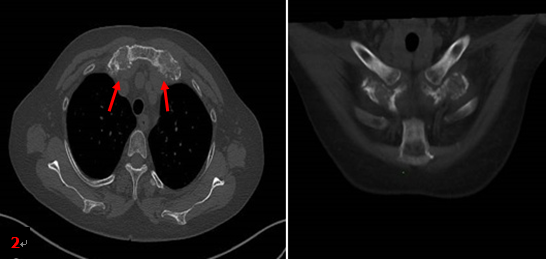

患者同期胸部CT檢查所見(圖2箭):雙側(cè)第1前肋對稱性肥厚、膨大、骨質(zhì)硬化,未見明顯軟組織腫塊。